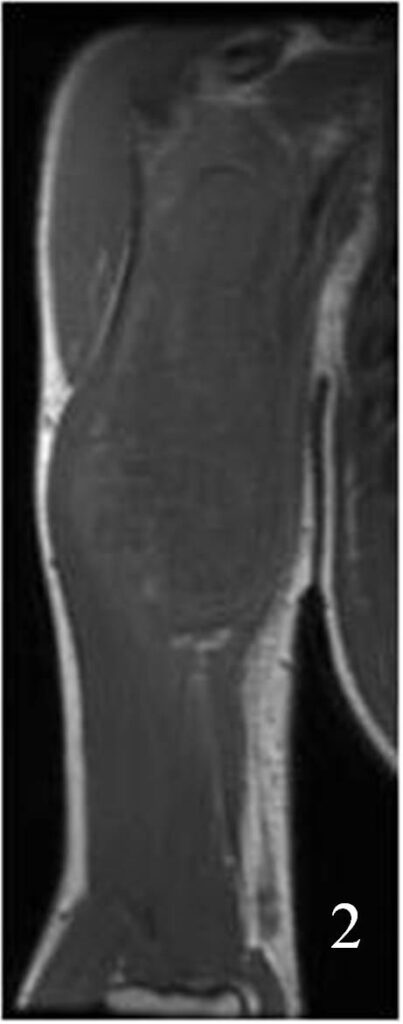

Fig. 2

Fig. 1-2: Axial (Fig. 1) and coronal (Fig. 2) MRI T1W of an angiosarcoma of the arm shows a well circumscribed heterogeneous lesion. Note the high signal in the center of the mass due to hemorrhage.